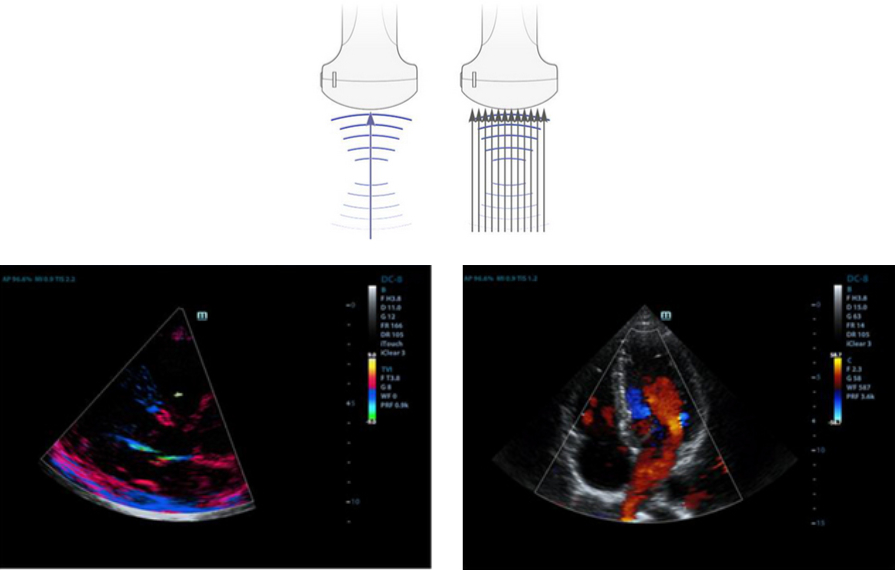

Formasi Multi-Berkas

Maksimum 12 kali penugasan untuk satu transmisi sinar, sehingga menghasilkan resolusi waktu luar biasa dan laju bingkai lebih tinggi.